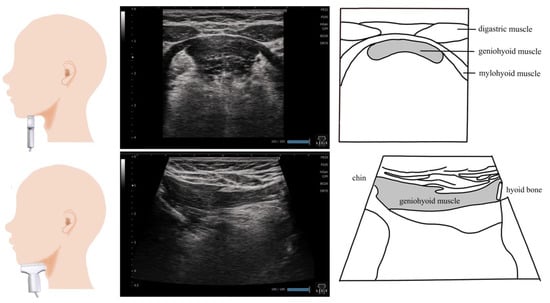

2. Geniohyoid Muscle (Figure 1)

3. Digastric Muscle (Figure 2)

4. Mylohyoid Muscle (Figure 3)